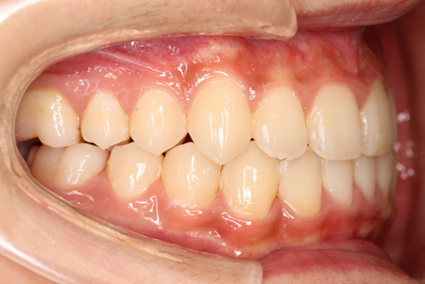

上の歯よりも下の歯が前へ出ている状態を受け口と言います。正常な噛み合わせとは、反対になり「反対咬合」とも呼ばれます。

受け口には、歯並びが元になる「歯性反対咬合」と、あごの骨の形が原因となる「骨格性反対咬合」があります。

このうち歯性反対咬合では、通常の矯正装置による治療が効果的です。